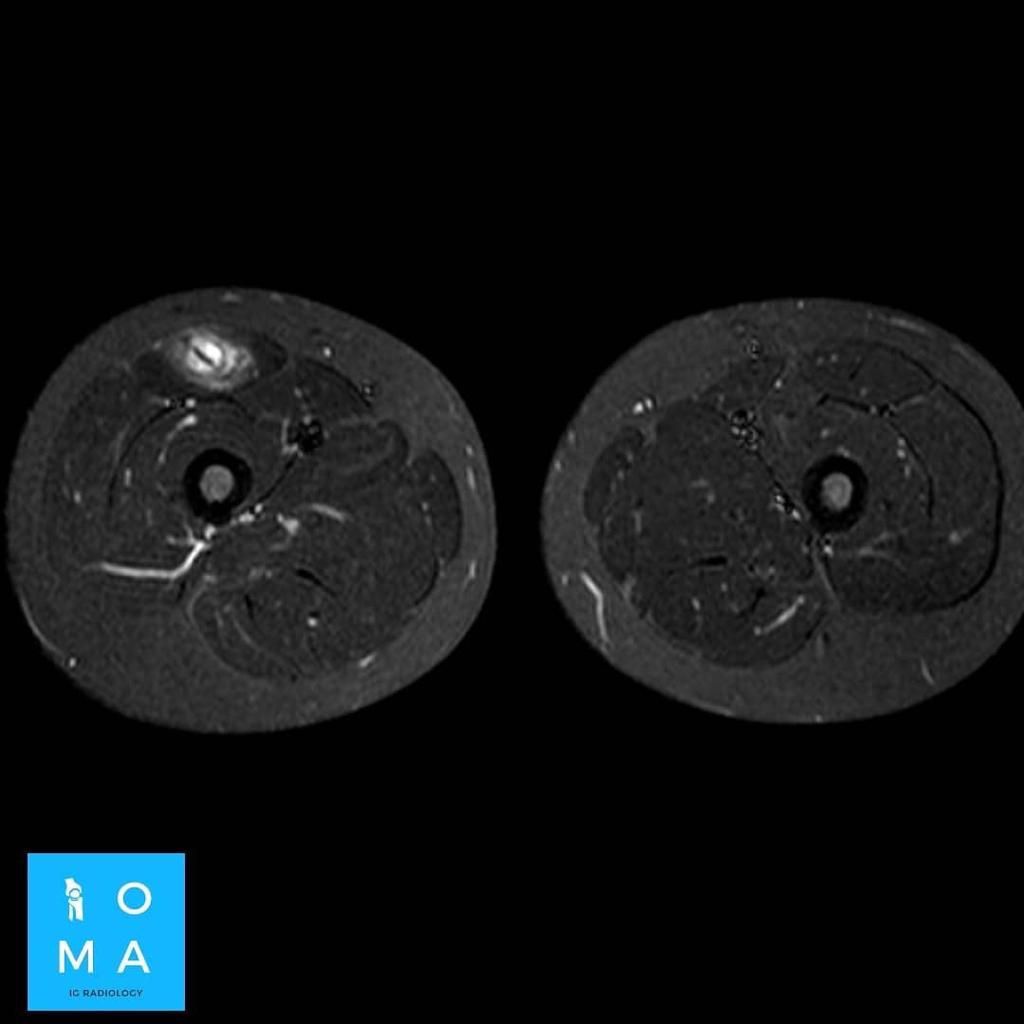

🔹Varón de 12 años que consulta por tumefacción en región anterior de muslo derecho. Refiere molestia a ese nivel 3 días antes, después de pique en partido de fútbol.

🔹Cambios inflamatorios asociado a edema y banda líquida que rodea a la unión miotendinosa central del sector medio del músculo recto anterior del cuádriceps derecho, de 10 mm de extensión, evocador de desgarro de la unión miotendinosa grado II.